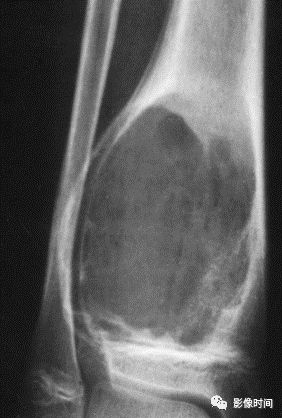

五、骨和软组织钙化

(一)瘤软骨钙化:瘤软骨常表现为环状钙化, 是诊断软骨类肿瘤较为可靠的影像学征象。环状钙化形成于环状软骨、以及软骨小叶边缘的软骨基质。钙质沉着可呈小点状、小条状、半环状或弧形;亦可浓密相连、重叠呈菜花状。钙化环的形态和密度可反映瘤组织分化程度, 通过观察钙化环的形态和密度,有助于良恶肿瘤的鉴别。

良性瘤软骨之瘤细胞分化好、生长缓慢、血供充分, 钙化环完整,密度高, 边缘清楚。良性软骨类肿瘤如骨软骨瘤(图 35)、软骨母细胞瘤(图 36)、内生软骨瘤(图 37)等均可于瘤组织内发生环形钙化。

恶性瘤软骨则呈密度淡薄, 边缘模糊的不规则钙化,恶性骨肿瘤的环形钙化,最多见于软骨肉瘤(图 38),其次是骨肉瘤。CT 是发现肿瘤内软骨钙化最为敏感的检查方法。

图 35  瘤软骨钙化:骨软骨瘤

图 36  瘤软骨钙化:软骨母细胞瘤

图 37  瘤软骨钙化:内生软骨瘤

图 38  瘤软骨钙化:软骨肉瘤